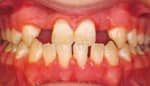

Jerrold further elaborates by suggesting that the doctor can unilaterally terminate the relationship if the patient breaches at least one of the five duties owed to the practitioner under the contract that comprises the doctor-patient relationship: (1) the patient is not following the doctor’s instructions regarding treatment, and thus is jeopardizing his/her own treatment (Figure 4); (2) the patient is not keeping appointments, thus causing interruptions in the continuality of care, not to mention the interference with the business aspect of the doctor’s practice; (3) the patient is not being truthful or forthcoming regarding necessary administrative inquires (eg, their medical history, information about those financially responsible for care, their degree of cooperation, signs and symptoms of problems, and so on); (4) the patient is not conforming to accepted modes of behavior (he is belligerent or abusive to the doctor or his staff, or is creating a hostile or unhealthy environment in the office); and (5) the patient is not paying for services rendered.6

| Figure 4: A case where the patient would not follow the oral hygiene program, so treatment was discontinued. |